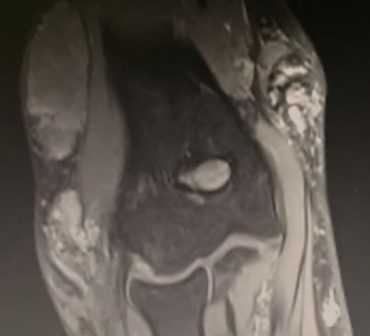

МРТ картина синовита, стрелками указаны участки отека костной ткани локтевого отростка

Синдром поражения суставов

Большинство изменений локтевого сустава сопровождается симптомами сопутствующего экссудативного синовита; его выраженность зависит от тяжести травм. На МРТ выявляется суставной выпот. Кроме того, иногда определяется отек костного мозга в субхондральных отделах эпифизов костей, отек периартикулярных мягких тканей.